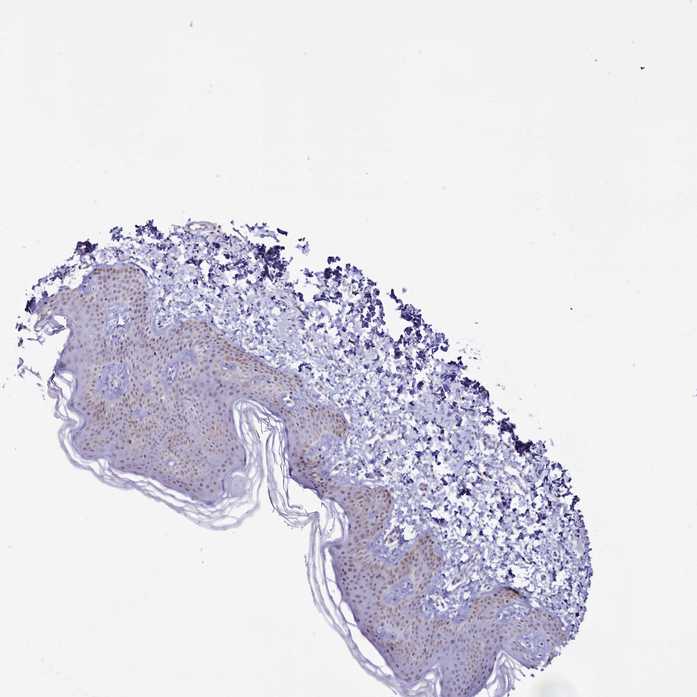

SKIN 2 - Antibody stainingi

Antibody staining in the annotated cell types in the current human tissue is reported as not detected, low, medium, or high, based on conventional immunohistochemistry profiling in selected tissues. This score is based on the combination of the staining intensity and fraction of stained cells.

Each image is clickable and will lead to virtual microscopy that enables deeper exploration of all samples and also displays staining intensity scores, fraction scores and subcellular localization as well as patient and tissue information for each sample.

Antibody HPA043258Antibody HPA043621

Epidermal cells MediumHigh